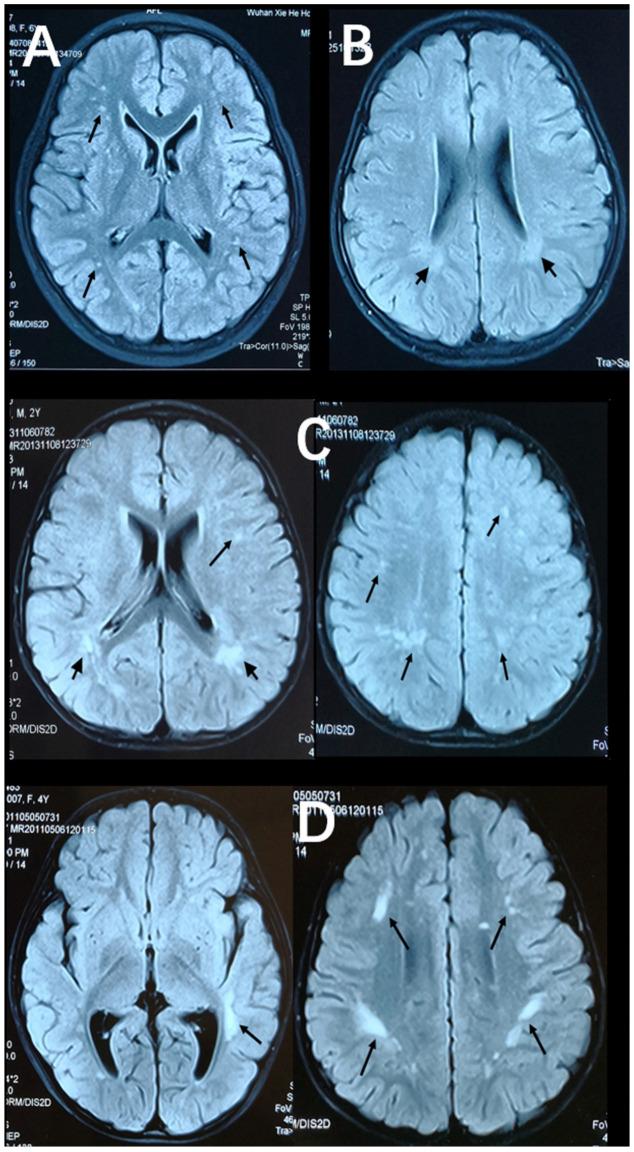

To analyze the association between stable asymptomatic white matter lesions (WMLs) and the cochlear implantation (CI) effect in congenitally deaf children, 43 CI children with stable asymptomatic WMLs determined via preoperative assessments and 86 peers with normal white matter were included. Outcome measurements included closed-set Mandarin Chinese (tone, disyllable, and sentence) recognition tests; categories of auditory performance (CAPs); and speech intelligibility rating (SIR) scales at 1, 12, and 24 months post-CI. Generalized estimating equation (GEE) models were used to analyze the association between WML and outcomes. In the WML group (control group), median CAP and SIR scores were 5 (5) and 4 (4) with mean rates of tone, disyllable, and sentence recognition of 84.8% (89.0%), 87.9% (89.7%), and 85.8% (88.0%) at 24 months post-CI, respectively. Auditory and speech performance improved significantly with implant use. Compared to their peers in the control group, for the participants with stable asymptomatic WMLs, auditory and speech abilities were not significantly different ( > 0.05). Stable asymptomatic WMLs might not be associated with poor auditory and speech intelligibility post-CI, which indicates that it is feasible to use comprehensive assessments to screen suitable candidates with WMLs who are likely to present with a good prognosis.

为分析先天性耳聋儿童中稳定无症状脑白质病变(WMLs)与人工耳蜗植入(CI)效果之间的关联,纳入了43名经术前评估确定存在稳定无症状WMLs的CI儿童以及86名脑白质正常的同龄人。结局指标包括封闭式汉语普通话(声调、双音节和句子)识别测试;听觉表现类别(CAPs);以及CI术后1个月、12个月和24个月时的言语可懂度评分(SIR)量表。采用广义估计方程(GEE)模型分析WML与结局之间的关联。在WML组(对照组)中,CI术后24个月时,CAP和SIR评分中位数分别为5(5)和4(4),声调、双音节和句子识别平均率分别为84.8%(89.0%)、87.9%(89.7%)和85.8%(88.0%)。使用人工耳蜗后听觉和言语表现有显著改善。与对照组中的同龄人相比,对于存在稳定无症状WMLs的参与者,听觉和言语能力无显著差异(>0.05)。稳定无症状WMLs可能与CI术后听觉和言语可懂度不佳无关,这表明使用综合评估来筛选可能预后良好的WMLs合适候选人是可行的。